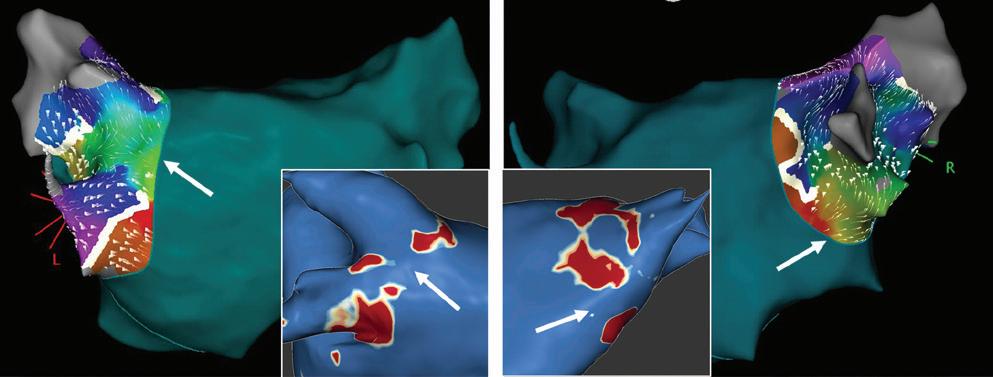

Figure 3: Agreement Between Electroanatomical Mapping and 3 Months Late Gadolinium Enhancement-MRI Regarding Gap Localisation

LPV entry

RPV entry

Activation maps of the LPVs and RPVs with conduction vectors (CARTO 3, coherent mapping with Pentaray catheter, Biosense Webster) indicating the entry site of the activation wave front (functional gaps) as detected during a repeat ablation procedure. Corresponding gaps detected by prior late gadolinium enhancement (LGE)-MRI (3 months post index ablation) are displayed in the small boxes. Colour-coding of the LGE maps (ADAS 3D software) is based on image intensity ratios with thresholds for dense scar (>1.32 red) and border zone (1.2–1.32 yellow), respectively. White arrows indicate localised functional gaps and LGE discontinuities, respectively. LPV = left pulmonary vein; RPV = right pulmonary vein.